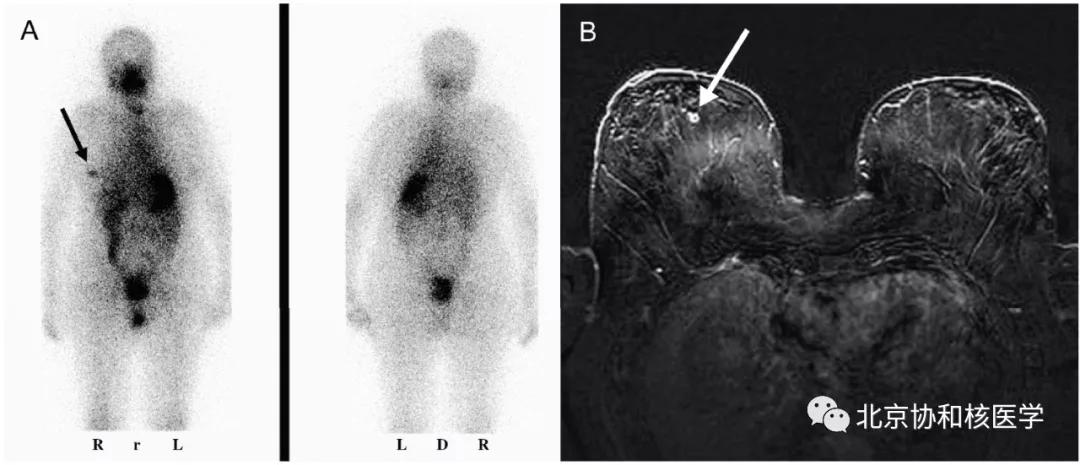

哺乳期乳腺摄取:

48岁女性,非哺乳期,碘扫见双侧乳腺生理性摄取增高(通常非哺乳期乳腺NIS表达低):

54岁女性,甲状腺乳头状癌甲状腺全切除术后,碘131治疗后碘扫见足周、头皮由于汗液中放射性碘的污染导致的异常摄取:

乳腺良性纤维瘤碘摄取: